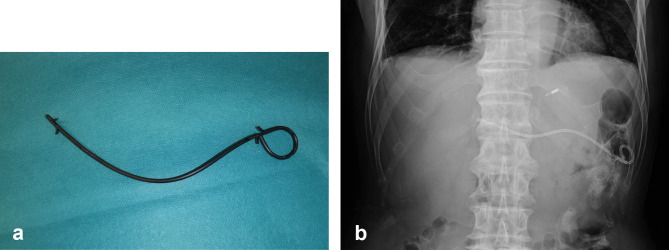

Objective: We report a case of spontaneous migration of a dedicated plastic stent after endoscopic ultrasound-guided hepaticogastrostomy (EUS-HGS) in a patient with surgically altered anatomy. Patient: The patient was a male in his 70s. He underwent EUS-HGS with the successful insertion of a dedicated plastic stent and had no obvious postprocedural complications. However, nine days after the procedure, the patient visited our hospital because of abdominal pain, fever, and stent excretion. We performed EUS-HGS with antegrade stenting, after which the patient had no further complications. Conclusion: Stent migration is considered a complication requiring caution when performing EUS-HGS in patients with surgically altered anatomy.